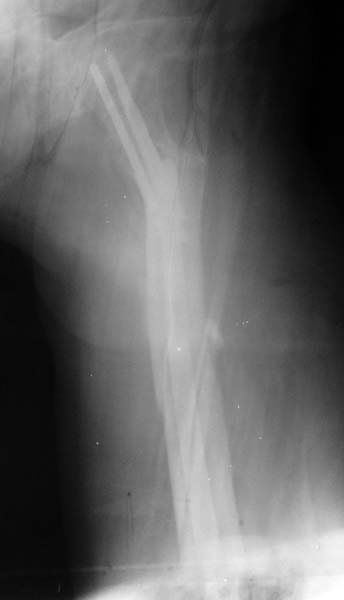

Уважаемые коллеги, на форуме был представлен случай перелома шейки и диафиза бедра, где после БИОС наступил варус шейки и винты упирались в крышу сустава. Форумом было рекомендовано пересинтезировать. Мы пригласили нашего дорогого друга Челнокова А.Н., основоположника БИОС в нашем регионе, который несмотря на очень занятость, и дальность расстояния решил выручать коллег и приехал к нам. Винты из шейки удалены, наложен дистрактор, произведена репозиция шейки, стержень ChM удален, произведен остеосинтез стержнем DePuy, шейка фиксирована, кроме стандартных двух винтов, еще одним винтом спереди стержня. рентген снимки прилагаются.

На первичных снимках был показан типичный пример осложнения, когда для фиксации ипсилатеральных переломов (шейки и диафиза) выбраны не отдельные фиксаторы, а один неадекватный гвоздь. По нашим данным, применение реконструкционных гвоздей первого поколения для фиксации ипсилатеральных переломов приводило к ложному суставу одного из компонентов, и это цифра доходила до 57%.